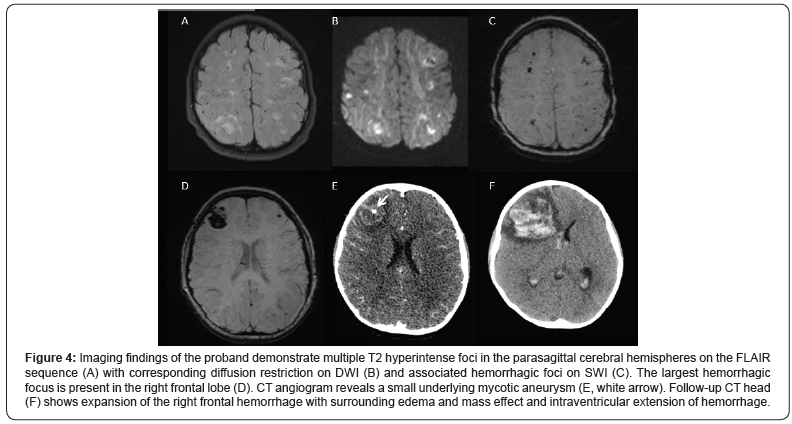

He was admitted to the hospital soon after the initial genetics visit for septic endocarditis of his mechanical mitral valve. Additional physical exam showed an extremely uncomfortable child, with flushing of his cheeks, scattered petechiae on his back, and Janeway lesions on both soles, his left index finger tip (Figure 3), and his left buttock. Trans-esophageal echocardiogram demonstrated a large vegetation on the mechanical mitral valve with associated regurgitation. He was started on appropriate antibiotics. Brain MRI showed multiple hemorrhagic bilateral cerebral infarcts concerning for septic emboli and mycotic aneurysms, confirmed on CT angiogram (Figure 4). His home Warfarin was switched to heparin continuous infusion for easy reversibility. The benefits of surgical valve replacement were felt to be outweighed by the risk of intracranial bleeding. However, during his hospitalization, he suddenly became unresponsive and an emergent head CT showed marked expansion of a right frontal hemorrhage. He passed away from cerebral herniation.